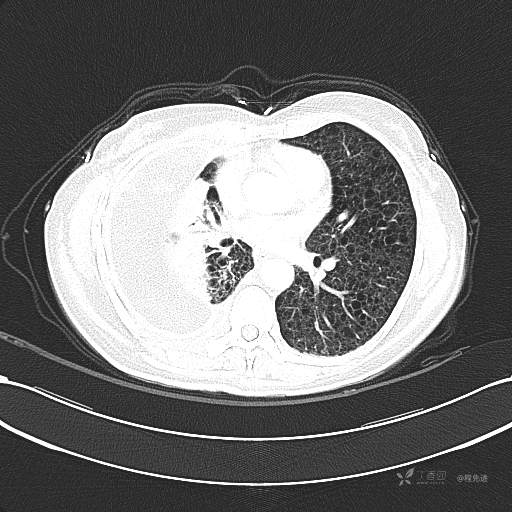

患者性别:女

患者年龄:51岁

简要病史:胸闷半年

肺淋巴管肌瘤病 (7)

乳糜胸 (8)